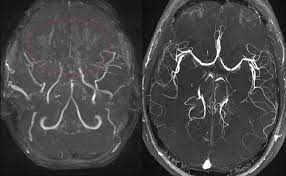

3. 신경영상검사(Neuroimaging): 뇌의 혈관 상태를 평가하기 위해 다양한 신경영상 검사가 사용됩니다. 주로 사용되는 검사에는 다음이 포함됩니다:

- MRI(Magnetic Resonance Imaging): MRI를 사용하여 뇌혈관을 자세하게 평가하고 혈류 문제를 확인할 수 있습니다.

- 혈관조영술(Cerebral Angiography): 혈관조영술은 혈관 내부 구조를 자세하게 시각화하기 위해 사용됩니다. 이 절차는 모야모야병을 진단하는 가장 확실한 방법 중 하나입니다.